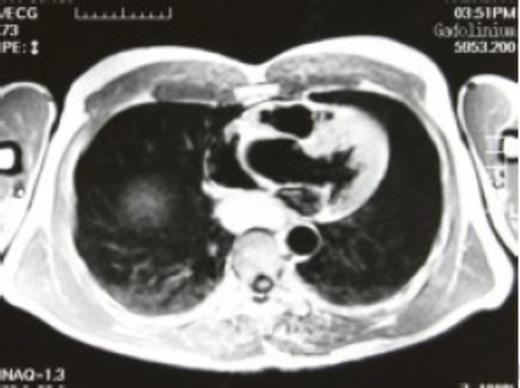

A 52-year-old man was referred due to an abnormal shadow on routine chest X-ray. His medical history included above-the-knee amputation of the left leg due to a traffic accident. He reported mild dysphagia when ingesting solid food. Physical findings were unremarkable. Computerized axial tomography (CAT) scan showed a posterior mediastinal mass compressing the oesophagus, and magnetic resonance imaging (MRI) revealed high signal intensities on both T1 and T2 weighted images suggestive of bronchogenic cyst (Fig. 1).

Gadolinium enhanced preoperative magnetic resonance imaging - high intensity signal lesion was found in the posterior mediastinum, suggestive of a bronchogenic cyst